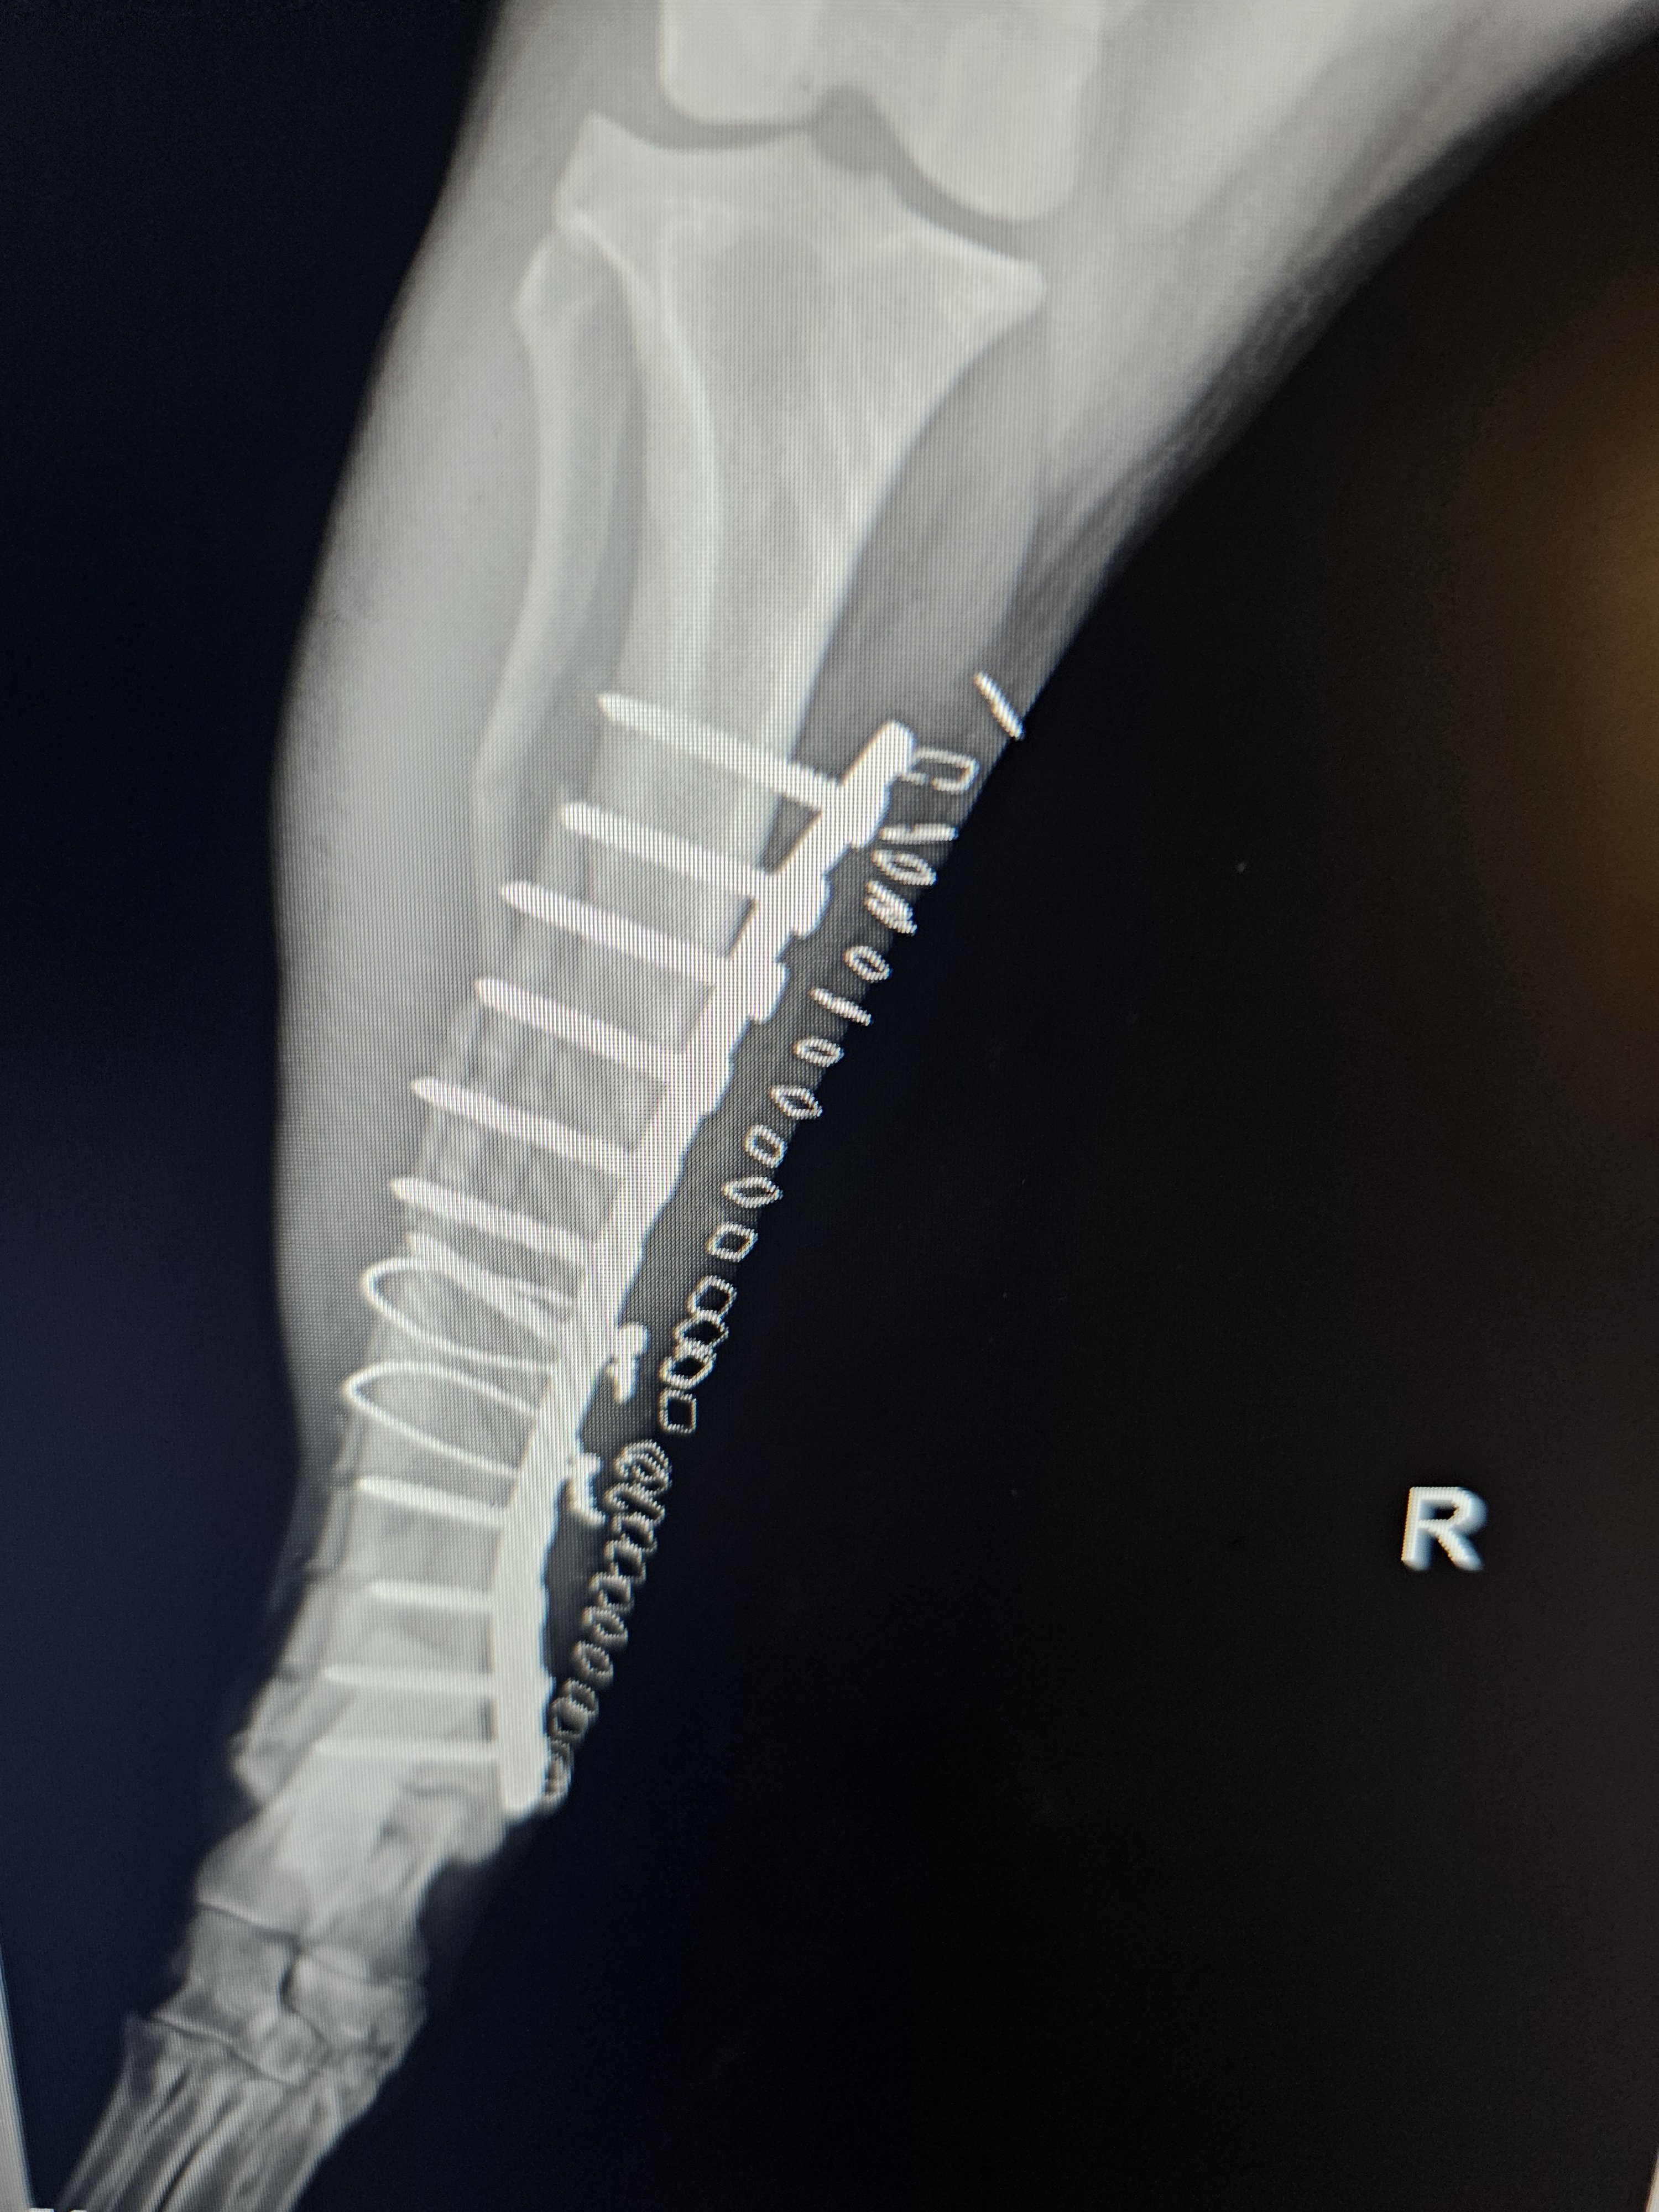

Fracture Repair

Broken bones require precise surgical repair for proper healing. Dr. Dan uses various techniques depending on the fracture type and location.

• Bone plating

• External fixation

• Intramedullary pinning

• Cerclage wiring